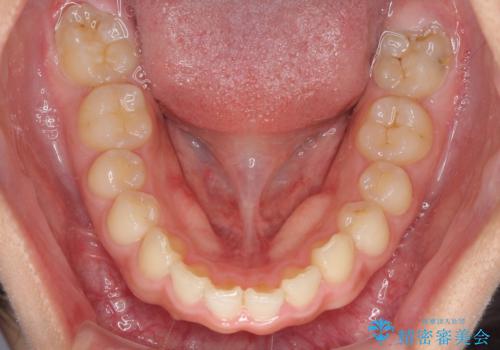

- 深い咬み合わせと上顎前歯の突出感を気にして来院された患者様です。

当院では通常、臼歯の咬合が理想的な位置に対して上顎が前方位にある場合。ワイヤー矯正または補助装置の併用したインビザライン矯正を選択しています。

今回は、できるところまででいいのでインビザライン単体で治療をしたいという希望があったため、インビザラインにて矯正治療を行うこととしました。

正面や横からの写真ではきれいに治っており、患者様は大変満足のいく仕上がりとなりましたが、深い咬み合わせの改善は不十分で、奥歯の咬み合わせも改善させることができませんでした。

インビザラインは、咬合力の強い方ですと、奥歯が歯肉内にめり込んでしまうため、前歯が強く接触してしまうことがあります。

こちらの方は、奥歯はしっかりと噛んだのですが、歯肉にめり込んでしまったことで、歯肉が腫れやすくなってしまいました。